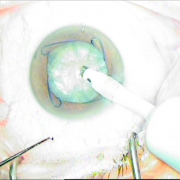

H επιστημονική μας ομάδα έχει την ικανότητα αντιμετώπισης όλων των τύπων των καταρρακτών, απλών, με μικρή κόρη, υπερώριμων, με φακοδόνηση, μετά από Laser μυωπίας και υπερμετρωπίας, καθώς και σοβαρότερων επιλεγμένων περιπτώσεων.

Διαθέτουμε την εμπειρία για χρήση ειδικών τύπων ενδοφακών, όπως είναι οι αστιγματικοί οι πολυεστιακοί, οι ιριδικής στήριξης και πολλών άλλων. Όλα αυτά συμβάλλουν στην αντιμετώπιση του καταρράκτη με ποιοτικό και εξατομικευμένο τρόπο.

Οι σύγχρονες μικροχειρουργικές τεχνικές αποβλέπουν στον ελάχιστο τραυματισμό του οφθαλμού και στην τοποθέτηση του τεχνητού ενδοφακού στην φυσική του θέση που είναι ο οπίσθιος θάλαμος. Οι ασθενείς απολαμβάνουν τα πλεονεκτήματα των επεμβάσεων μικρής τομής χωρίς ράμματα, με άμεση αποκατάσταση της όρασης και χωρίς μετεγχειρητικό αστιγματισμό.